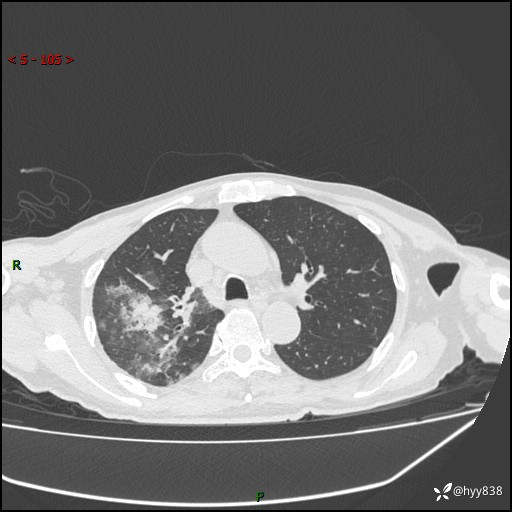

第一次胸部CT检查